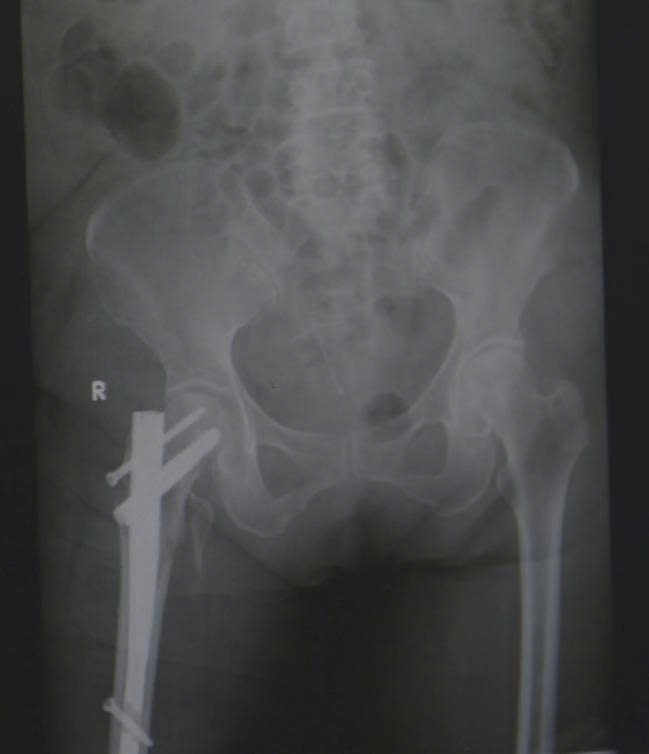

Sau khi đánh giá các nguy cơ và đạt được sự ổn định toàn thân, các bác sĩ khoa Chỉnh hình Vi phẫu tiến hành thực hiện ca phẫu thuật đóng đinh nội tủy đầu trên xương đùi – một kỹ thuật phổ biến trong điều trị gãy liên mấu chuyển. Phương pháp này giúp giữ vững cấu trúc xương, cho phép bệnh nhân xoay trở vận động, có thể ngồi dậy và tập vận động sớm.

gay-co-xuong-dui.jpg

Hình ảnh phim X-quang sau phẫu thuật đóng đinh nối tụy cho bệnh nhân gãy liên mấu chuyển xương đùi - Ảnh BVCC

Sau hai tuần phẫu thuật, bà T. có thể ngồi dậy, xoay trở cử động chân, cụ bà đã có thể ăn uống trở lại. Dù còn yếu, nhưng ánh mắt bà đã ánh lên niềm vui và sự nhẹ nhõm rất nhiều so với thời điểm nhập viện.